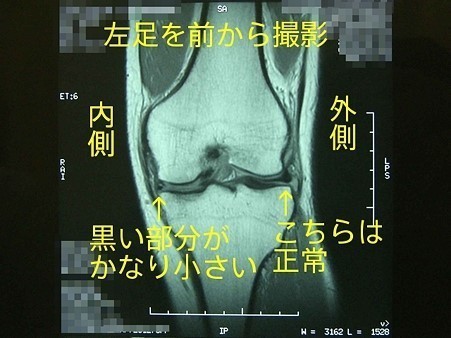

半月板損傷

膝の関節は太ももの大腿骨、すねの脛骨、およびお皿の膝蓋骨という三つの骨からできていて表面はツルツルした軟骨で覆われています。

大腿骨と脛骨の間にある三角形をした繊維状の軟骨を半月板と呼びます。

半月板は、関節の適合性を良くし安定性を与えながら、大腿部から受ける体重の荷重を分散し衝撃を吸収するクッションの働きをしています。

この半月板の一部が損傷した状態を「膝半月板損傷」と呼び、痛みがあるほか膝の曲げ伸ばしができなくなります。

外側半月板損傷は生まれつき半月板が大きい人に発症する事が多いですが、内側半月板の損傷は、膝にひねりが加わるようなスポーツ活動などで損傷する事が多いです